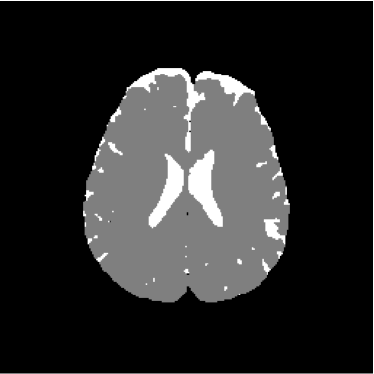

Figure 3: Axial DW-MR image of 13th slice with diffusion exponent of 1000 s/mm2

To perform the training we chose 13th slice of each volume sample (figures 1, 2 and 3), once this slice shows the temporal corni of the lateral ventriculi. The exhibition of such structures facilitates the analysis of the specialist and helps him to find a correlation between data generated by our computational tool and a priori specialist knowledge. Furthermore, slice 13 presents a considerable amount of artifacts out of the cranial region.

Figure 13 shows the training set mounted on the 13th slice of the volume of ADC maps. Figures 14 and 15 show the ground truth volume and the 13th slice, respectively.

Figure 14: Ground truth image (13th slice) generated by polynomial net classification

Figure 28 shows 13th slice of classification result obtained by the use of the objective dialectical classifier. Figure 29 exhibits 13th slice of classification result after performing post-labeling, whilst figure 30 shows the entire volume generated by ODC classification.

The training process of ODC algorithm resulted in 6 classes. These classes were reduced to 4 after manual post-labeling, merging 3 classes out of brain region, namely image background, noise and cranial box. The post-labeling is manual because all 3 cited regions are statistically different and, consequently, they are merged due to our interest in classes more related to the brain regions. On figure 29 it is possible to notice that ODC was able to distinguish white matter from the gray matter present in the interface between liquor and white matter.

Figure 29: 13th slice of objective dialectical classification after post-labeling

Figures 33, 34 and 35 show binary images of 13th slice of ODC classification, showing liquor (cerebrospinal fluid, CSF), gray matter (GM) and white matter (WM), respectively, whilst figures 37 and 38 show the respective morphological spectra and accumulated morphological distributions. Both morphological spectra and accumulated morphological distributions were obtained using structure element square 3×3333\times 3 center (2,2)22(2,2).

Figure 34: 13th slice of gray matter volume detected by method ODC

Observing figure 34 indicating the detection of gray matter by the objective dialectical classifier, we can perceive the significative reduction of gray matter in brain frontal lobule, better seen in superior part of image. This lobule is directly related with the reduction of recent memory.